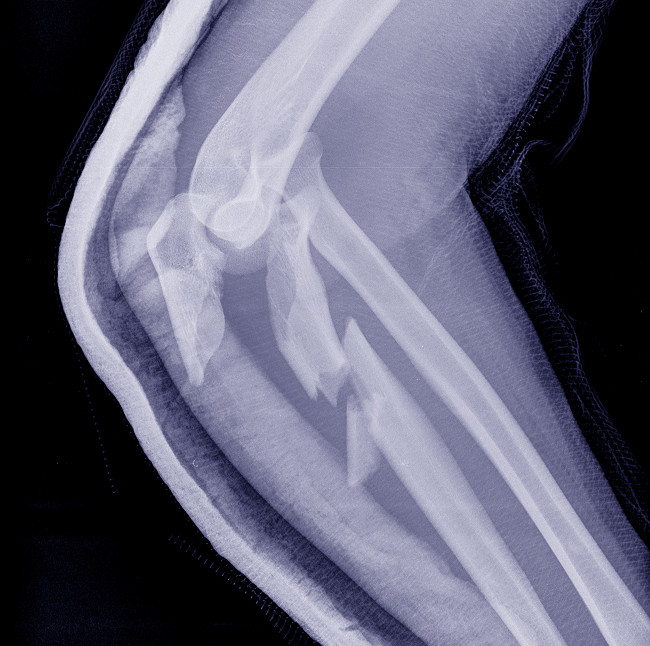

Distal Fractures

A distal fracture is an injury to the distal end of the humerus, most often at the elbow. These injuries often involve the articular surface, making them more challenging to treat. For minor displacements, a doctor may prescribe conservative treatment and a cast, but intra-articular injuries require surgical osteosynthesis with anatomical restoration of the articular surface.

Supracondylar and Condylar Fractures

These types of injuries are primarily observed in children and young adults after a fall on a bent arm. A supracondylar fracture is located above the articular surface, while a condylar fracture only partially involves it. Treatment is aimed at restoring the joint's shape and preventing contractures. A plaster cast is applied to a humeral fracture; if necessary, reduction is performed under X-ray guidance.

Supracondylar Fractures

These are the most complex injuries, in which the fracture line passes through both condyles, destroying the articular surface. In such cases, conservative treatment is ineffective and surgical treatment is required. The doctor performs osteosynthesis with special mini-plates and screws, achieving precise alignment of the fragments. After surgery, staged rehabilitation and physical therapy are prescribed to restore range of motion in the joint.